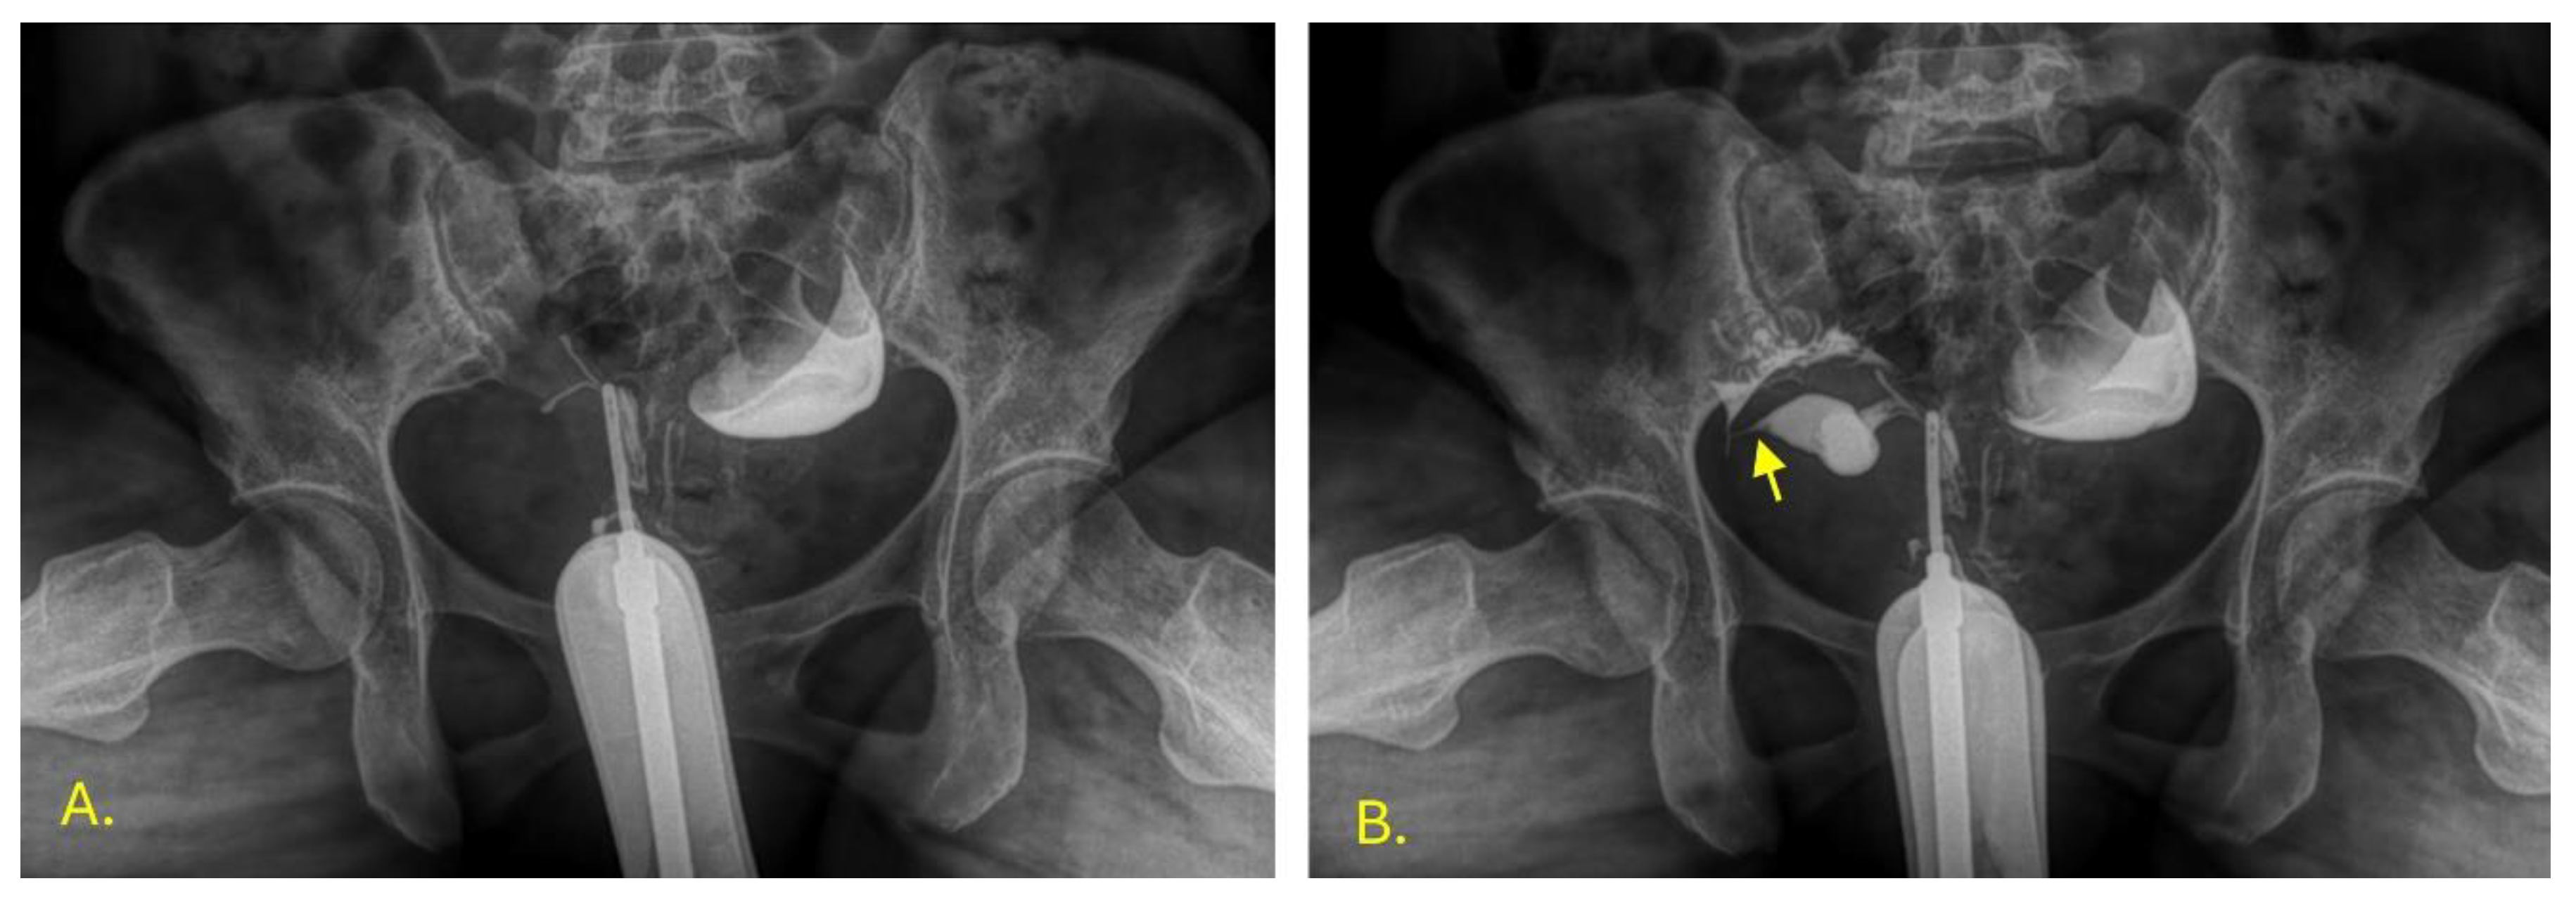

During the hysterosalpingography, a uterus was observed in the left vaginal cavity in anteroversion lateralized to the left, with adequate passage of the contrast medium towards the peritoneum through the uterine tube. The edges of the uterus in the evaluable area are defined as uterus didelphys bicollis (Figure 4).

Figure 4. Left hysterosalpingography. Image A: Jarcho cannula in the left uterus. Image B: Contrast medium is instilled, revealing the endometrial cavity (indicated by an arrow) with an image inside that suggests the presence of a submucous fibroid (M).In the right vaginal cavity, the IUD was seen in the vaginal fundus, and contrast passed into the peritoneum through the right uterine tube without complications, with an anteroverted uterus lateralized to the right (Figure 5).

Figure 5. Right hysterosalpingography. Image A: Jarcho cannula in the right uterus. Image B: Contrast medium is instilled, revealing the endometrial cavity and part of the right fallopian tube (indicated by an arrow).